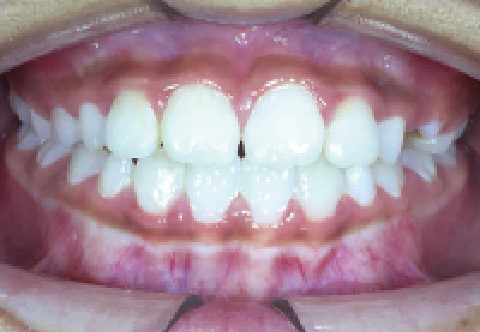

症例 : 8歳 女性

Before

After

主訴

叢生(歯がガタガタ)

乳歯の晩期残存(乳歯が抜けず残ってしまっている状態)

治療方法

床矯正+インビザファースト

総額治療費

660,000円(税込)

治療期間

2年半

治療のリスク・副作用

治療期間が長くなってしまう

改善ポイント

乳歯が抜けないまま放っておくと、永久歯が生えてくるスペースがなく、歯並びが悪くなってしまいます。

下顎前歯が生えてくるのを待ってから顎の拡大を行い、歯並びの調整にインビザファーストを行いました。